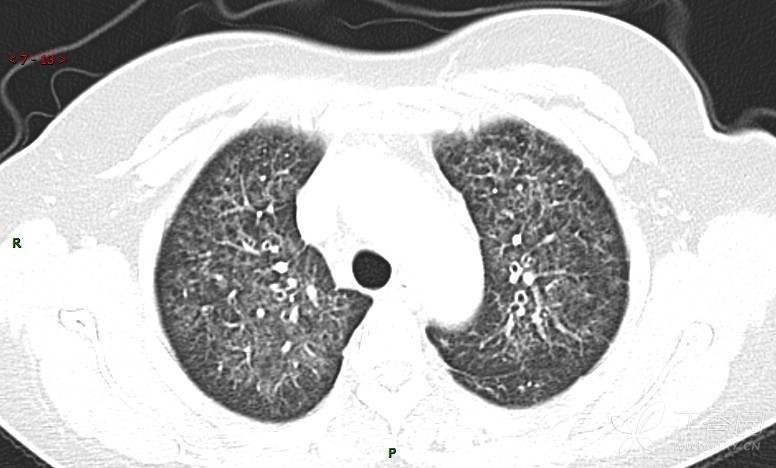

肺内弥漫性网状结节影,PET-CT却无阳性病灶,这是?(附其他2例链接)

女性,58岁,阵发性咳嗽2月,加重1月。

患者于2月前无明显诱因出现咳嗽,以阵发性干咳为主,接触冷空气后咳嗽明显,偶咳少量白色泡沫样痰,咳嗽剧烈时感憋喘,无发热、盗汗,无头痛、头晕,无胸痛、咯血,无恶心、呕吐,无腹痛、腹泻,无尿频、尿痛等不适,于当地医院给予肌注及静脉药物治疗,具体药物名称不详,效果欠佳,近1月来患者咳嗽频率较前增加,咳嗽剧烈时感双侧季肋区疼痛不适,10余天前出现发热,体温在38℃左右,伴畏寒、寒战,无头痛、头晕,无纳差、乏力等不适,药物治疗后体温降至正常,仍阵发性咳嗽,今为求进一步诊治,就诊于我院急诊,因呼吸内科暂无床位,急诊门诊以“肺间质病变”收入急诊留观室,给予“抗感染、止咳”等对症支持治疗后,今日以“肺间质性病变”收入我科,患者自本次发病以来,神志清,精神可,饮食尚可,睡眠一般,大小便正常,体重较前无明显变化。

患者活检肺组织后行PET/CT检查